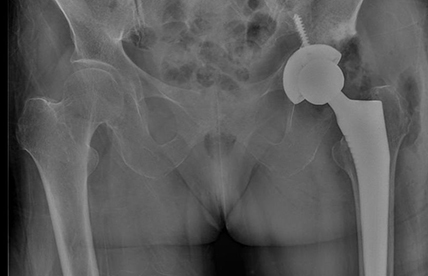

Kalça Kireçlenmesi

Koksartroz, kalça ekleminde bulunan kıkırdak yapının zaman içinde yıpranmasıyla ortaya çıkan bir eklem hastalığıdır. Kıkırdağın incelmesi ve yüzeyin bozulması sonucunda eklem hareketleri sırasında sürtünme artar. Bu durum en sık kasık bölgesinde hissedilen ağrıya, hareketlerde kısıtlanmaya ve yürüyüşte aksamalara neden olur. Hastalık ilerledikçe ağrı sadece hareketle değil, dinlenme sırasında da görülebilir. Özellikle eğilme, çorap giyme veya ayakkabı bağlama gibi günlük aktiviteler zorlaşabilir.

Tedavinin temel amacı ağrıyı kontrol altına almak ve eklem hareketliliğini korumaktır. Başlangıç döneminde kilo kontrolü, düzenli egzersiz ve fizik tedavi uygulamaları ön plandadır. Gerekli durumlarda ağrı kesici ilaçlar ve eklem içi enjeksiyonlardan faydalanılabilir. İleri seviyedeki hastalarda kalça protezi ameliyatı oldukça etkili ve başarılı bir tedavi yöntemidir. Bu ameliyat sayesinde hastaların ağrıları büyük oranda azalır ve günlük yaşam aktiviteleri daha rahat hale gelir. Tedavi, hastanın durumuna göre planlanır.